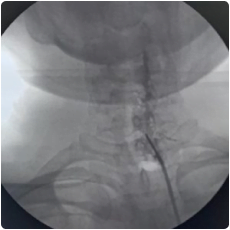

Cervical Facet injection is done under aseptic precautions in an operation theatre, under the guidance of fluoroscopy.

Intraop fluoroscopy image of cervical spine